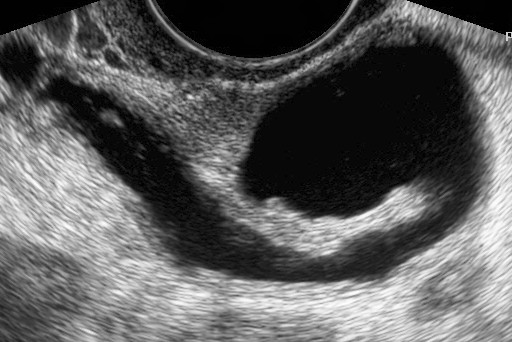

Ин витро е процес, при който се изваждат яйцеклетки от яйчниците на жената, оплождат се от сперматозоиди на мъжа в лабораторни условия, оплодените яйцеклетки се отглеждат няколко дни до развитието на ембриони, които се пренасят в матката на жената.